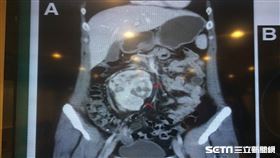

她便秘半年 竟「巨腫瘤」塞半顆肚

便祕別當小事,恐是腹部長腫瘤作怪。一名20多歲女性,...